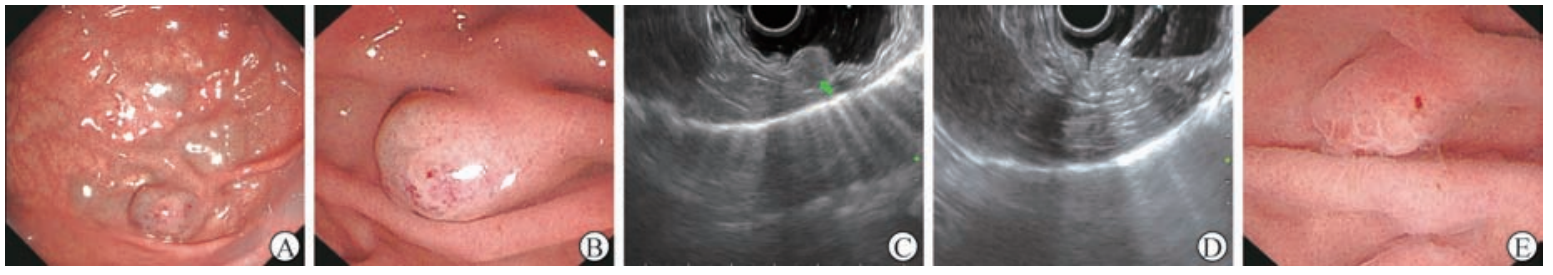

入院后行血常规、粪便常规、粪便隐血试验、肝功能、肿瘤标志物等检查,均未见明显异常。2022 年6 月21 日肝脏CT增强检查提示,胃底部见一直径约12mm的结节影,动脉期未见明显强化,门静脉期明显不均匀强化,考虑良性病变(图1)。2022年6月23日内镜检查提示胃底大弯侧黏膜下蓝紫色血管样隆起簇和明显结节状隆起,较大隆起结节直径约10 mm,考虑为胃底血管瘤(图2A、2B);换用纵轴超声内镜进镜,扫描隆起结节状病灶处见蜂窝状低回声团块,起源于黏膜下层(图2C),测量大小为9. 1 mm × 11 mm,彩色多普勒超声血流图像显示少量的血流信号;遂超声内镜引导选用22G注射针(南微医学科技股份有限公司)刺入病灶处,并向内注射聚桂醇约10 mL(图2D);注射后再次用超声内镜扫描发现术后病灶处腔内高回声充填,黏膜下隆起明显塌陷(图2E)。术后嘱患者常规禁食12h,予以补液、护胃、头孢呋辛预防性抗感染等对症支持治疗,术后未出现发热、腹胀、腹痛、呕血、黑便等症状,术后第2 天顺利出院。2022 年11月3日患者入院复查,内镜下仍见胃底大弯侧黏膜下血管样结节隆起,较上一次内镜检查范围明显缩小(图3A),遂再次行超声内镜引导聚桂醇消融术(图3B、3C),术后血管瘤腔内呈高回声充填,病灶较前注射前明显塌陷(图3D)。术后住院观察期间患者未出现发热、呕血、黑便、腹胀、腹痛等情况,术后第2天顺利出院。3个月后(2023年2月9日)患者再次复查,内镜下见胃底大弯侧黏膜瘢痕样改变,注水后用12 MHz超声微探头扫描见原病灶处胃壁层次结构正常(图3E)。目前患者门诊定期随访中,至截稿一般情况良好。

图2 2022年6月23日超声内镜引导聚桂醇消融术治疗胃血管瘤过程A内镜下见胃底黏膜下蓝紫色血管样隆起簇B内镜下见胃底病灶黏膜下蓝紫色结节状隆起C纵轴超声内镜扫描示病灶为位于黏膜下层的低回声团块(箭头所示) D超声内镜引导向胃血管瘤病灶注射聚桂醇E术后病灶明显塌陷